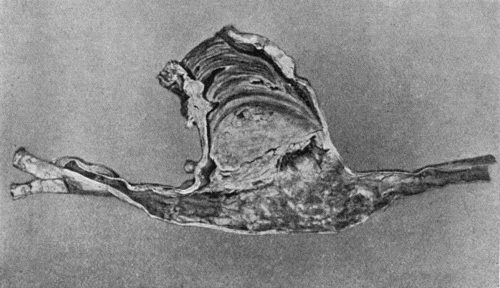

| 109. | Volkmann's Ischæmic Contracture | 414 |

| 110. | Ossification in Tendon of Ilio-psoas Muscle | 417 |